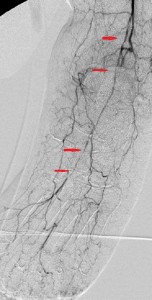

In this patient, a 67 year-old woman with long-standing diabetes, there was a plantar ulcer of her anterior left forefoot that resisted healing despite many noninvasive treatments. Her podiatrist referred her to me and her sonographic and angiographic investigations revealed multiple significant stenoses in her distal left superficial femoral artery (LSFA), left popliteal artery, and her anterior tibial artery. Her posterior tibial artery was occluded and her chief path of blood flow to the left foot was her left peroneal artery. Her arterial paths above the distal left SFA were open and she had stage 3 chronic renal insufficiency. Faced with the dilemma of continuing foot infection and potential limb loss and worsening renal insufficiency following exposure to radiocontrast, she put off endovascular revascularization of the arterial narrowings for sometime, finally caving to pressures from her son.

After instituting strategies to minimize contrast-induced nephropathy, I employed atherectomy of the distal LSFA and popliteal stenoses and angioplasty of the multifocal stenoses of her anterior tibial artery down to the dorsalis pedis artery to restore reasonable flow to her foot that helped the ulcer heal.

Images in the top panel illustrate her disease before the interventions, those in the middle panel illustrate some intraprocedural steps (balloon angioplasty), while those in the bottom panel illustrate improved blood flow to the foot following treatment.